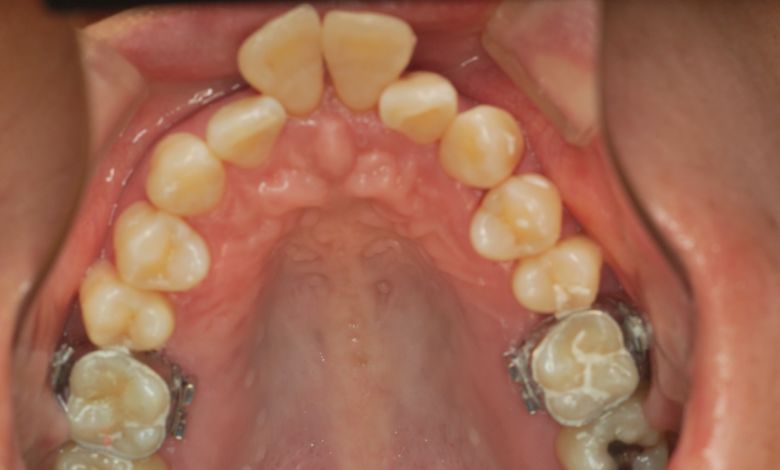

上下顎ともに犬歯が唇側に大きく突出しており、歯列弓が狭小なため、

他院では上下左右4本の便宜抜歯を前提とした矯正治療を提案されていました。

上顎には左右の犬歯が著しく唇側に偏位している

精密検査の結果、当院では抜歯を行わず、歯列弓の拡大によってスペースを確保し、非抜歯での矯正治療を選択しました。歯列の叢生(ガタガタ)は解消され、機能的かつ審美的に優れた咬合が得られました。

他院にて上下左右4本の抜歯を前提とした矯正治療を提案されていました。上顎・下顎ともに歯列弓が狭く、

V字型の弓状を呈していたため、叢生(歯の重なり)が強く、噛み合わせにも不調和が見られる状態でした。

上顎歯列はV字型に近く、全体的にアーチが狭窄している状態

歯列弓はV字型に狭く、左右の犬歯が唇側に大きく転位している状態